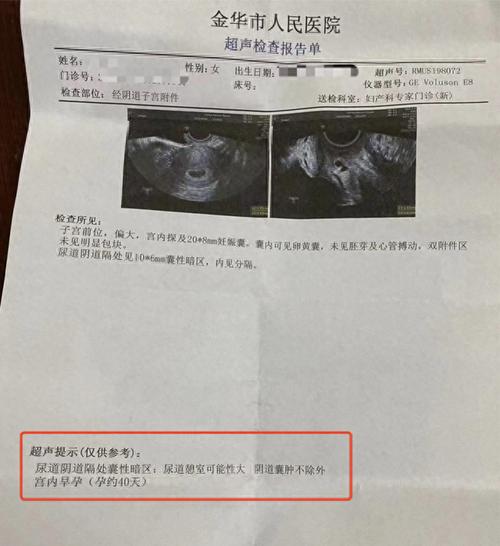

女子称b超未查出怀孕被开禁服药导致打胎,金华妇幼保健院:正协商|金华

图片尺寸640x699